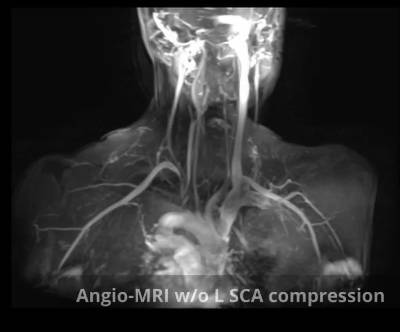

- Cervical-thoracic CT angiography/Cervical-thoracic MR angiography with compression manoeuvres